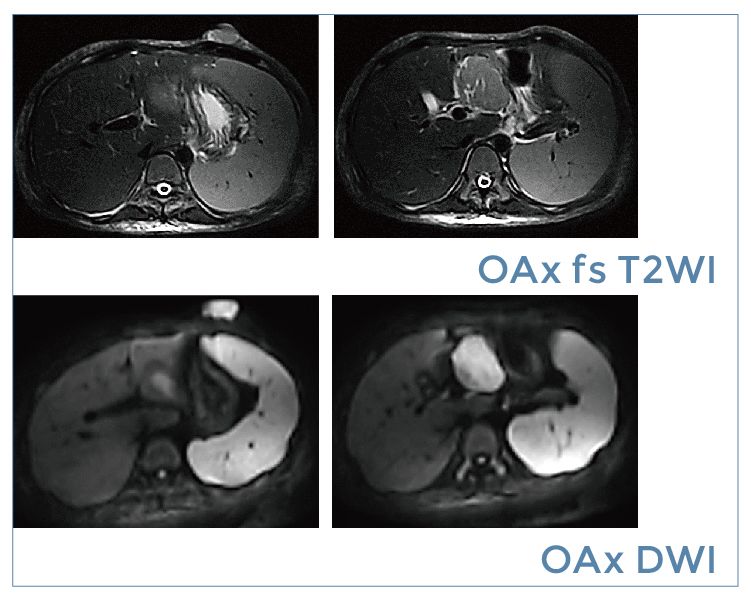

【朗润影像档案】20190920磁共振影像病例结果讨论